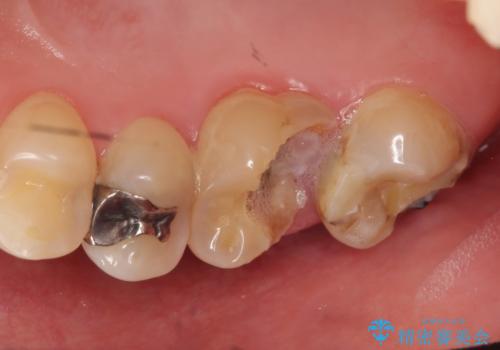

- 右上の奥歯が欠けてしまったので診て欲しいといらっしゃった方の症例です。

右上6番目の歯は虫歯が深く、保存が難しかったため抜歯しました。

その後歯茎や骨の回復を待ち、オールセラミッククラウンのブリッジによる補綴を行いました。